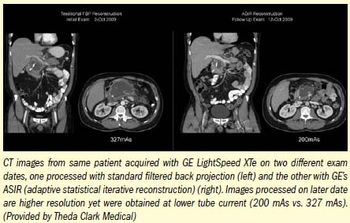

Algorithms that use iterative reconstruction to eliminate noise in images will have a “profound effect” on CT, according to Stanford radiology professor Dr. Geoffrey Rubin.